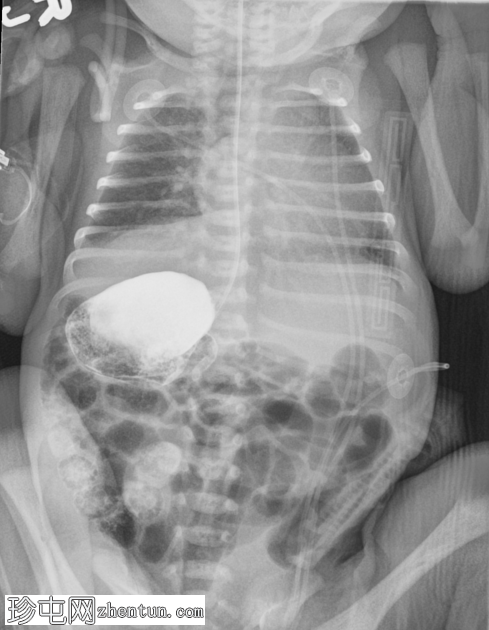

本例为腹腔内脏反位合并肠旋转不良。

初始胸片显示心脏轮廓解剖结构正常。相比之下,腹部X线片显示提示内脏反位的征象,表现为食管造影管的走行异常以及肝脏轮廓明显偏左。透视检查进一步证实了这些观察结果,并进一步提示肠旋转不良。

随后,患者被送入手术室行肠旋转不良手术。术中发现与影像学检查结果相符,证实存在腹部内脏反位和肠旋转不良。具体而言,肝脏、胆囊、门静脉和十二指肠后胆总管位于左侧,而脾脏、胃和胰尾位于右侧。此外,还观察到十二指肠和盲肠之间存在Ladd带,符合肠旋转不良的诊断。